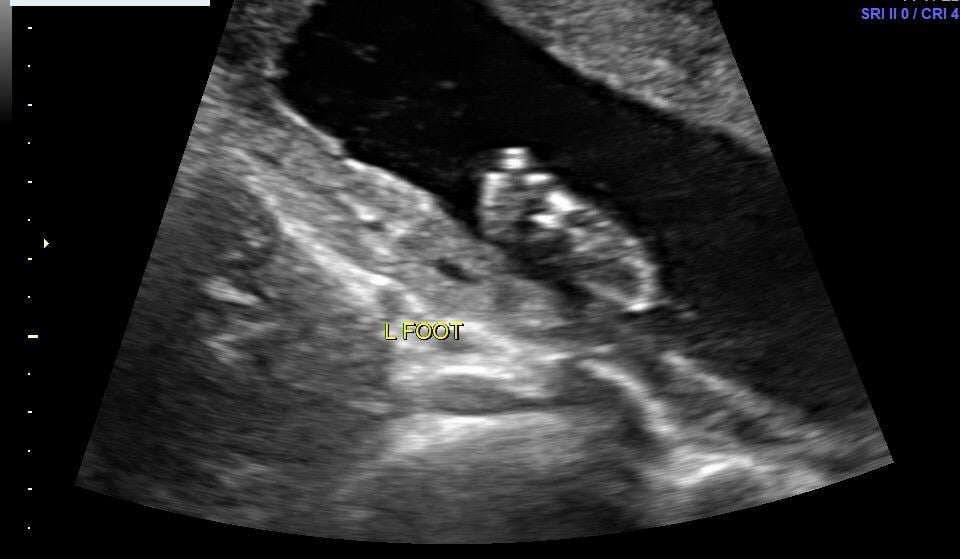

My baby giving the ultrasound tech a hard time, wouldn't keep their little toes out of their mouth☺️

Team Green